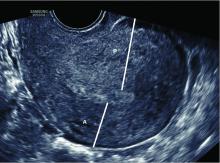

(Left image) Incarcerated retroverted uterus at 14 weeks gestation. Note the anteriorly displaced and compressed cervix and cervical canal (dotted yellow line) and the fundus wedged posteriorly (white arrow). The first impression is that the placenta is posterior (blue arrow) and the fetus is cephalic. (Right image) The same pregnancy after correction of the incarcerated uterus. Note the placenta is actually anterior (blue arrow) and the fetus is breech.